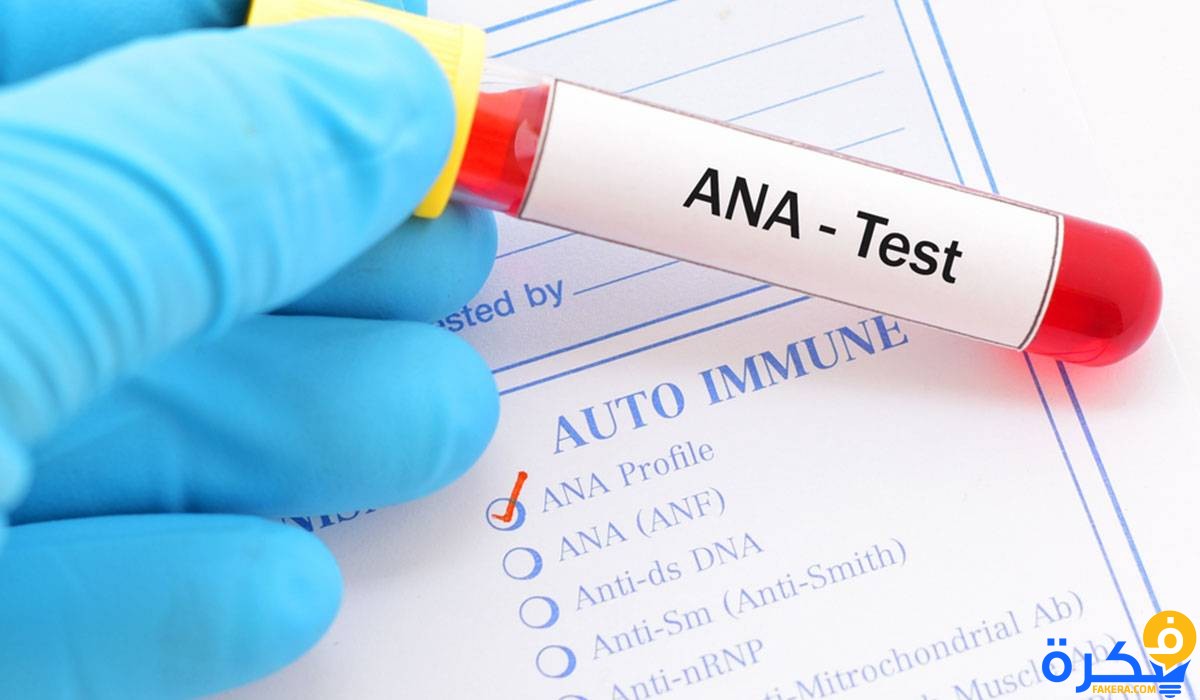

أكمل القراءة »نتابع في هذا المقال نتحليل ANA وجهاز المناعة من خلال موقع فكرة، وسنتابع أيضا نسبة فحص ANA وطريقة عمل التحليل…